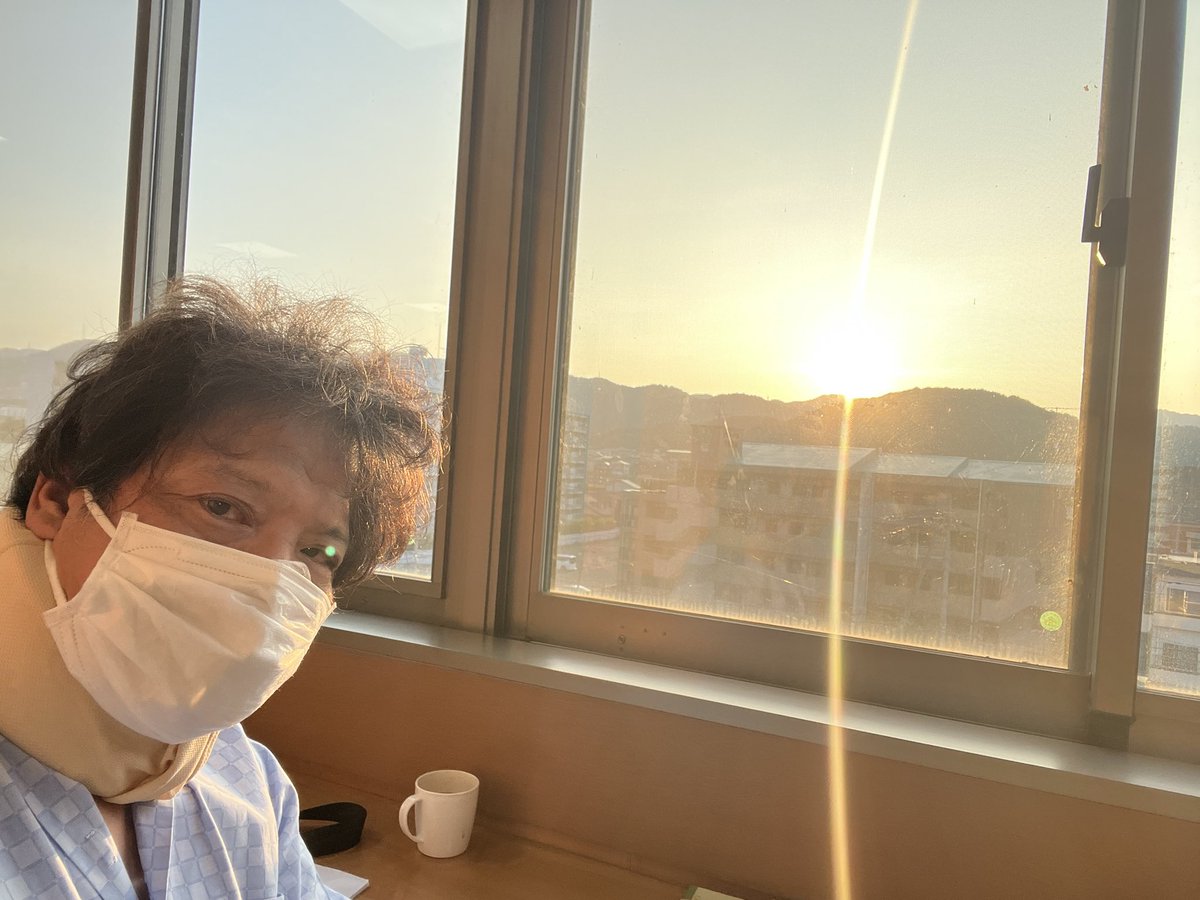

2020年27年ぶりにアマチュア再開局。3,5M〜1200MまでQRV。アマチュア無線家と繋がるのが楽しみ。また、気になったローカルな話題もお伝えしていきます。コマーシャルは、美容系なのでその情報もお伝えします。コマーシャル以外は、元バンドマン。2022年12月に脚立からの落下大腿骨骨折。只今リハビリ中。